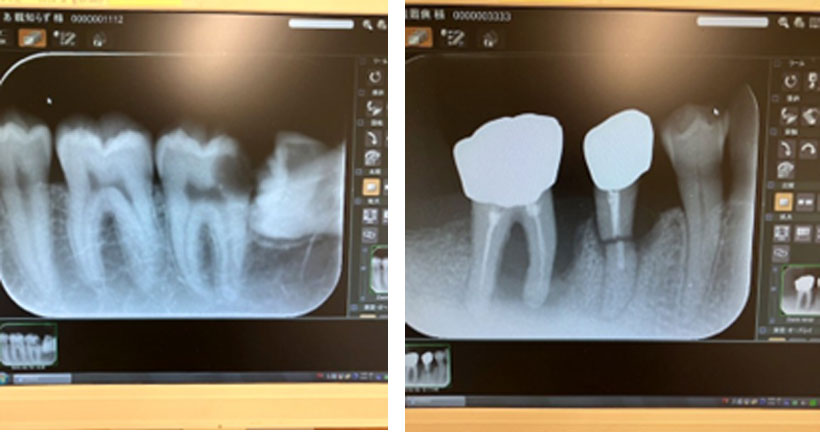

そして歯科のあの小さいレントゲンは、一回0.001mmシーベルトです。

頬っぺたの外側から照射して歯を通して舌の内側で受け取る3~5センチぐらいの話ですから、この程度で済みます。だからと言って何でもいいわけではないので、じゃかじゃかやるとことは戒めなければなりません。